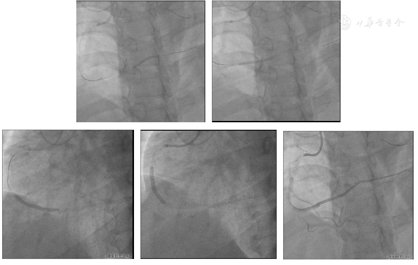

启动逆向介入治疗,逆向经1.8 F-Finecross150微导管操控SION导丝至前降支近段粗大第一间隔支各二级分支下行均不能成功进入PD(图9)。操控SION导丝经前降支中远段细小间隔支至右冠状动脉远段(图10)。但1.8 F-Finecross150微导管不能完全通过侧支循环至右冠状动脉远端,更换1.7 F-埃普特170微导管尝试仍不能通过侧支循环至右冠状动脉远端,再次更换1.8 F业聚成功通过侧支循环至右冠状动脉远端(图11)。应用反向CART技术扩张RCA中段,应用AGT技术前向送延长导管至RCA中远段,操控逆向导丝进入延长导管及指引导管,但微导管不能进入延长导管,应用拖拽技术使逆向微导管进入前向指引导管内(图12)。

前向Sion blue导丝进入逆向微导管内,回退逆向微导管至间隔支内,沿前向导丝送入SprinterLegend 2.0 mm×20.0 mm球囊扩张右冠状动脉远端(图13),因逆向微导管经过的PD血管细小,应用双腔微导管操控Fielder XT-R导丝不能至PL远端,更换Pilot 200至PL远段,退出双腔微导管,送微导管Finecross130至PL造影证实位于真腔内,更换Sion blue至PL远段,沿导丝送入Emerge 1.5 mm×20.0 mm、SprinterLegend 2.0 mm×20.0 mm球囊扩张病变(图14)。

送入IVUS导管至PL,回撤检查:IVUS导管均位于血管腔内(图15A~E),PL可见约200°钙化(图15A),PL近段至右冠状动脉远段可见内膜下血肿(图15B~D),右冠状动脉中段可见斑块浸润,无血肿(图15E)。应用Quantum 2.5 mm×15 mm再次自PL近段扩张病变(图16)。

右冠状动脉置入4枚支架:RSINT 2.25 mm×30.00 mm、Firebird 2.75 mm×33.00 mm、Firebird 3.5 mm×33.0 mm、Firebird 4.0 mm×29.0 mm(图17),应用非顺应性球囊扩张支架(图18)。

造影评价右冠状动脉支架置入后效果及评价左冠状动脉血管情况(图19)。